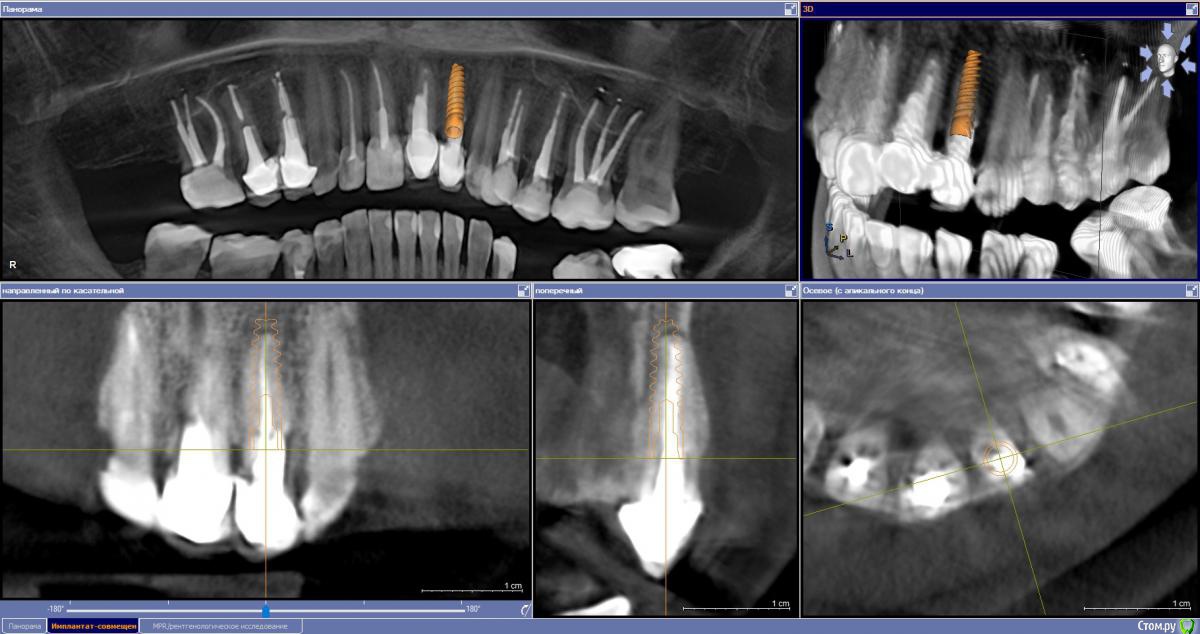

Ponchik Опубликовано 16 июня, 2017 Автор Поделиться Опубликовано 16 июня, 2017 Спасибо за советы. Размерность - альфа-био Nice 3.2 - 13 мм - этот вариант на КТ. Можно взять 16мм Ссылка на комментарий